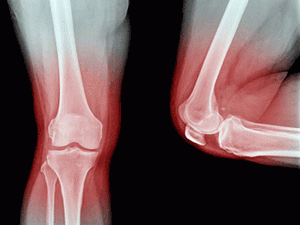

Также выполняются стандартные рентгенологические исследования, которые проводятся с помощью современного оборудования – при меньшей дозе облучения (и, соответственно, еще большей безопасности) обеспечивается высокое качество результата.

Остеоденситометрическая диагностика выполняется у пациентов с остеохондрозом и тех, у кого проводились операции по протезированию костей и суставов.